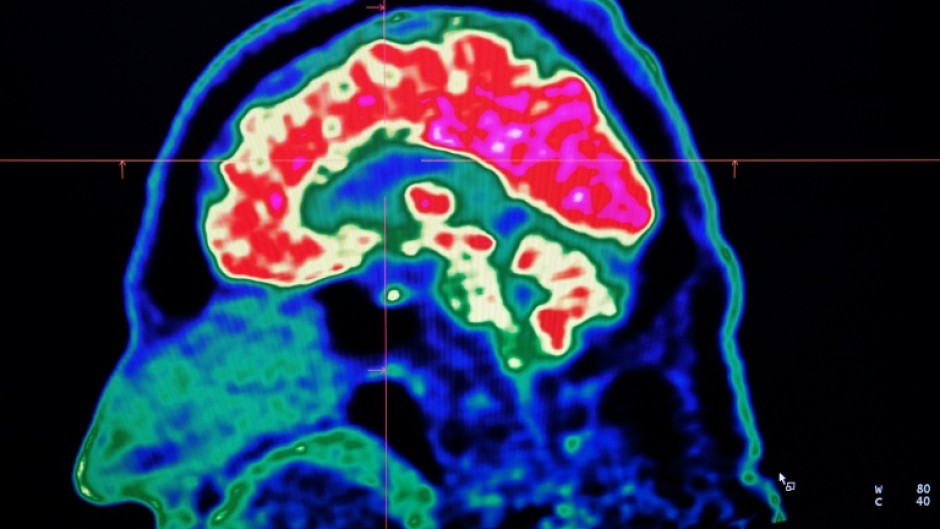

New Brunswick launched a new investigation, this time looking at data from 222 patients, about 75 percent of whom lived in or around the city of Moncton.

Investigators studied living patients and analyzed autopsies.

"We are able to conclude that our investigation found no evidence of a widespread issue among this patient group," the report said.

"We do not feel that exposure to these substances is a contributing factor to most patients' illness," it added.